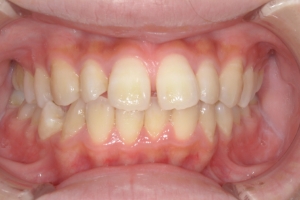

BEFORE

治療前

下の前歯が上あごの歯ぐきに当たるほど噛み合わせが深く、そのことが原因で上顎歯列の正中にすき間(正中離開)が生じていました。部分矯正ですき間を無理やり閉じても、噛み合わせが深いままでは治療後の再発リスクが高くなります。そのため全体矯正で奥歯の噛み合わせを整え、噛み合わせを浅くしつつ前歯を並べました。正中離開は戻りやすい傾向があるので、再発を防ぐため固定式リテーナーを推奨しています。